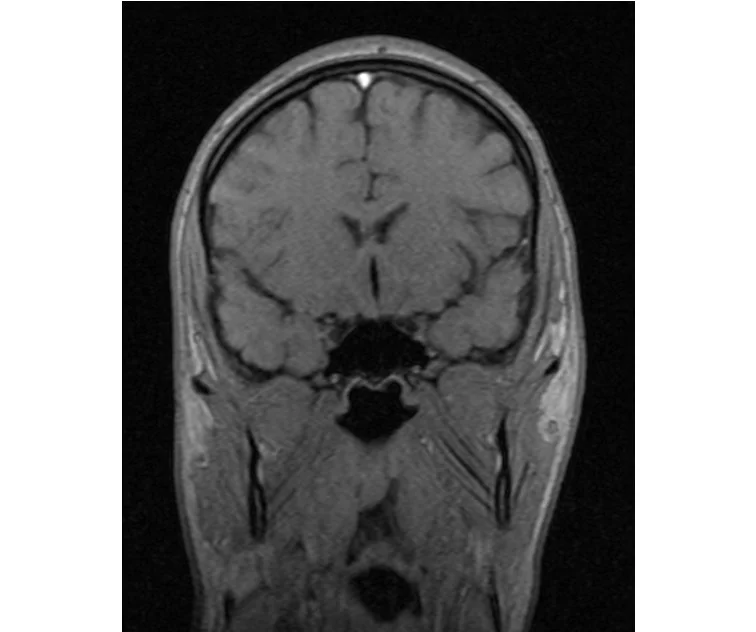

делал в обласной на siemense.В заключении выданом мне через 15мин.после мрт (легкая дегидрация)

Меня смутил факт выдачи заключения через 10мин(наверно они у них зарание напечатаные)я не медик.достаточно мимолётного взгляда на снимки?А вы видете на них гидроцефалию? Я лиш спросил куда идти с результатами томографии?и не хотел никого роздражать.

Я попросил взглянуть на снимки и сказать видна.ли на них гидроцефалия?или куда обратится за консультацией по этому вопросу?В мрт снимках наверно розбирается любой нервопатолог(я так предположил)

Я уже говорил, что независимо от того, есть на МРТ гидроцефалия или нет, лечиться тебе нужно только в том случае, если есть какие-либо проявления болезни, иначе на все эти анализы можешь забить... Но давай все-таки разберемся с томограммой.

Итак, с самого начала томограмма обозначала срез какого-либо органа на определенной глубине, позволяла заглянуть вовнутрь. При компьютерной томографии аппарат делает десятки срезов головного мозга в разных направлениях и из этого множества срезов он моделирует полноценное объемное изображение мозга в натуральную величину. Обрати внимание, компьютер работает не с этими миниатюрными изображениями, а с трехмерной моделью в масштабе 1:1. Эту модель вдоль и поперек анализирует суперсовременный компьютер, выполняющий миллионы операций в секунду. Только ***** может пытаться перепроверить компьютер, ведь человеку не хватит всей жизни чтобы проанализировать то, что компьютер с тобой сделал за 10 минут. Я хочу, чтобы ты это понял!

Ты разместл здесь несколько миниатюр и хочешь, чтобы врач по ним создал полноценное объемное изображение в натуральную величину, а потом осмотрел его со всех сторон и дал заключение? Но ведь это невозможно. Это просто насмешка над врачом, это издевательство над здравым смыслом. Принеси Букеру уменьшенный в 50 раз снимок зуба и спроси у него, в каком состоянии там корневые каналы. Или давай я дам тебе скрин со спутниковой карты города и попрошу тебя описать, какого цвета и какой модели запечатленная со спутника машина, какой у нее гос.номер, сколько в ней пассажиров, сколько из них мужчин и сколько женщин...